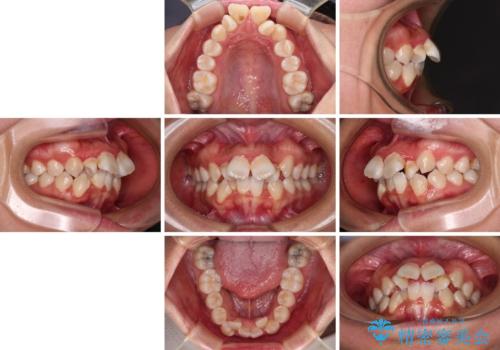

- 飛び出した上顎の前歯と八重歯を気にして来院された患者様です。

口元を積極的に引っ込めるために、上下左右の小臼歯計4本を抜歯することとしました。

舌の突出癖が強いため、しっかりと口元を引っ込めるため、舌のトレーニングをしっかりと行いながら矯正治療を行うこととしました。